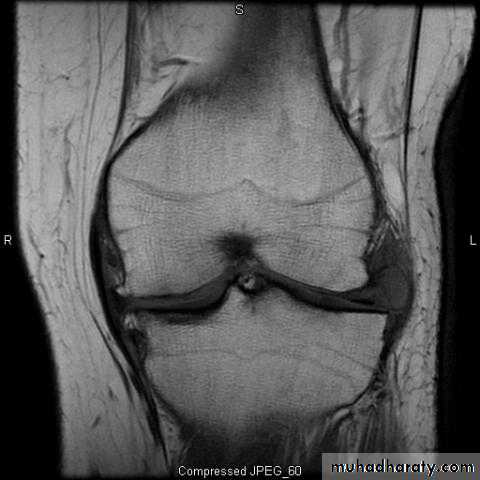

• X-ray; to exclude associated fracture.

• Arthroscopy; it’s the best to give direct visualization of the inside of the joint to prove the diagnosis & exclude other possible injuries.

• MRI; good and accurate noninvasive technique specially if associated with arthroscopic findings.